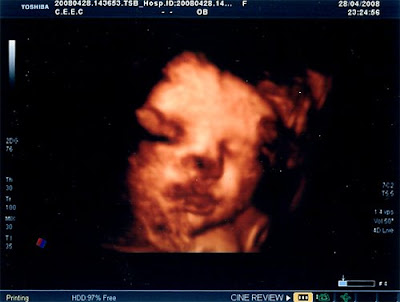

Ecografia das 32 Semanas

Finalmente fui fazer a última ecografia, a ecografia das 32 semanas.

Estivemos à espera imenso tempo, mais 2:30 do que devíamos, mas valeu a pena só facto de irmos ver a nossa pucunina, parecia que estava a sorrir para nós.

Está tudo bem ainda bem, o liquido amniótico, a placenta, o estar de cabeça para baixo já é normal, e ainda está contente de estar na barriga da mãezinha. Os factores importantes para se saber isso é o facto de se mexer muito, ter liquido suficiente, ver-se a caixa torácica a mexer-se muito bem, e os punhos fechados que significa que tem força.

A nível de peso é que não está muito pesada, no geral e por essa mesma razão está no percentil 25/50, mas a mãe também é pequenina, o obstetra prevê que nasça por volta de 3,100Kg, também não é necessário mais, ele deu-se por satisfeito com o resultado da ecografia. E como tivemos tanto tempo à espera tivemos direito a um bonús. Ora vejam.

P.S: Poderia ter ficado bem mais nítida se não tivesse com a carinha encostada à minha placenta.